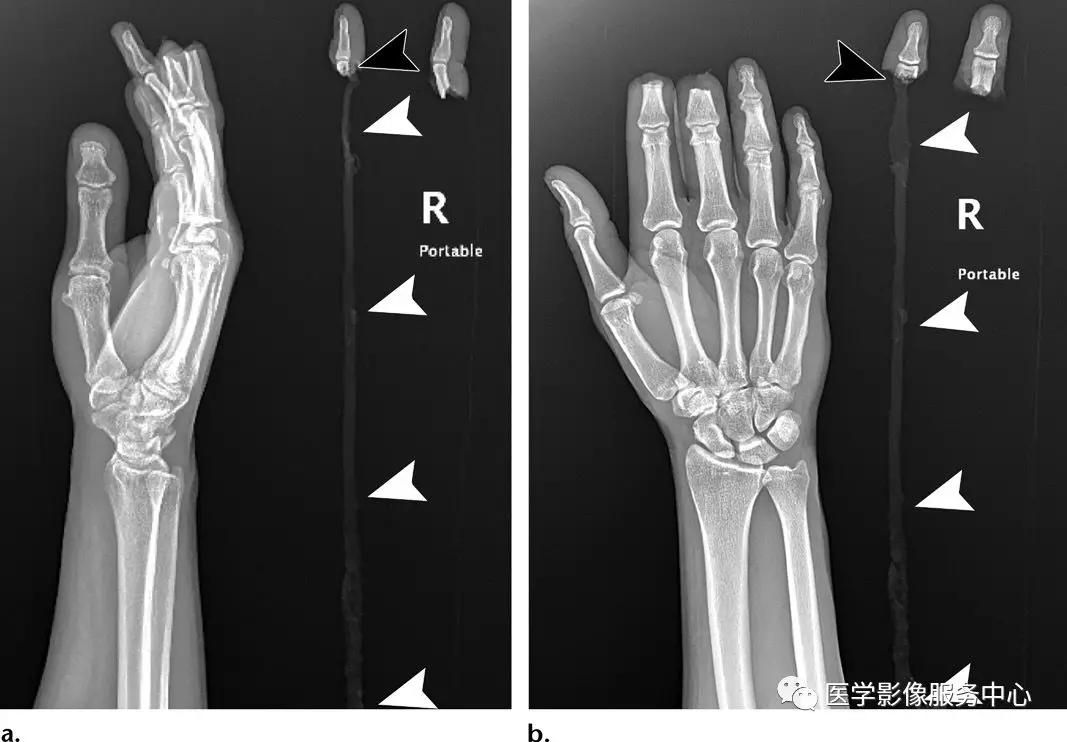

反Bennett骨折:

第五掌骨桡侧基底部的略示移位的关节内骨折。由于尺侧腕伸肌腱的反作用牵拉力,第五掌骨向近端及尺侧移位。